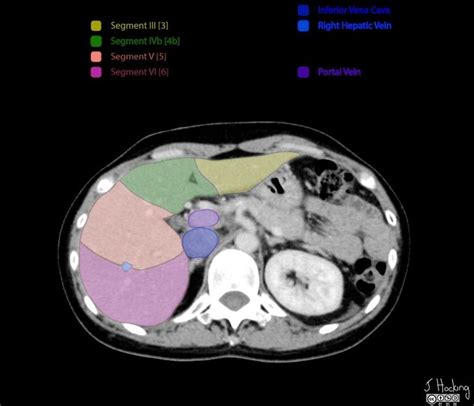

segments of liver anatomy

Liver Segments: Annotated CT | Radiology Case | Radiopaedia.org | Liver

radiopaedia segments hepatic radiology annotated couinaud segmental segmentation slidedocnow radiological ultrasound